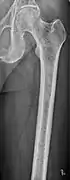

The diagnostic examination of a person with suspected multiple myeloma typically includes a skeletal survey. This is a series of X-rays of the skull, axial skeleton, and proximal long bones. Myeloma activity sometimes appears as "lytic lesions" (with local disappearance of normal bone due to resorption) or as "punched-out lesions" on the skull X-ray ("raindrop skull"). Lesions may also be sclerotic, which is seen as radiodense.[70] Overall, the radiodensity of myeloma is between −30 and 120 Hounsfield units (HU).[71] Magnetic resonance imaging is more sensitive than simple X-rays in the detection of lytic lesions, and may supersede a skeletal survey, especially when vertebral disease is suspected. Occasionally, a CT scan is performed to measure the size of soft-tissue plasmacytomas. Nuclear Medicine Bone scans are typically not of any additional value in the workup of people with myeloma (no new bone formation; lytic lesions not well visualized on nuclear bone scan).

Multiple myeloma in the upper arm

Femur with multiple myeloma lesions